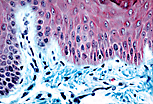

A类(厚型)角化复层扁平被覆上皮

角质形成细胞是表皮的主要细胞类型,其从表皮基底层向表层经历一系列分化过程。这一分化过程改变了角质形成细胞的形态,并形成四层结构:基底层、棘层、颗粒层和角质层。 当角质层较厚时,该角化复层扁平被覆上皮被称为A类(厚型):主要分布于手掌和足底部位。 |

| A类角化复层扁平被覆上皮具有较厚的表层(角质层),该层由角化的死亡细胞构成。 | |

皮纹是角质形成细胞垂直排列形成的隆起和凹陷,构成表皮表面的嵴和沟,是指纹形成的结构基础。

此外,可见汗腺管(汗腺排泄管)在表皮内呈螺旋状走行。 |

| 表皮与真皮的连接面并非直线:表皮如同一个平板,其深面因结缔组织的突起(真皮乳头)而形成凹陷。真皮乳头增强了表皮与真皮的连接,并有利于上皮的营养供应。 | |